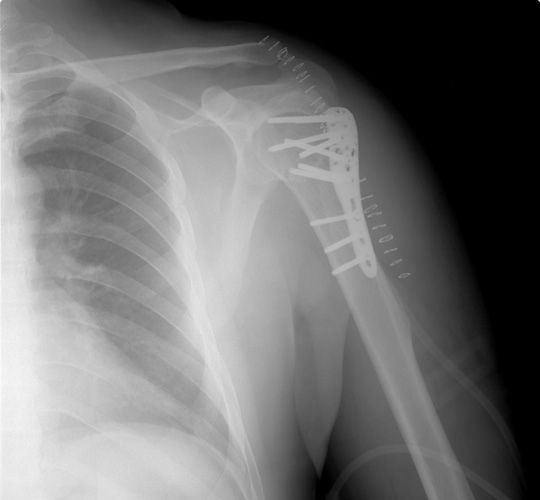

OMUZ CERRAHİSİ ve OMUZ HASTALIKLARI